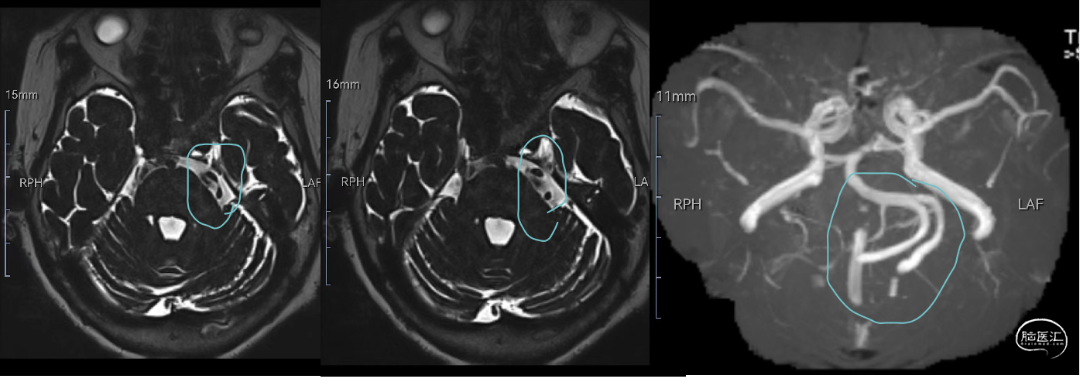

术前MRI检查提示:

椎-基底动脉扩张迂曲症,左侧三叉神经出脑干段受压。

该患者为典型椎基底动脉冗长导致。椎-基底动脉延长扩张症(vertebrobasilar dolichoectasia,VBD) 指椎-基底动脉因各种原因导致异常扩张、延长、迂曲,是一种少见的脑血管疾病,人群发病率为 0. 2% ~ 4. 4% ,其临床表现以脑缺血、脑神经或脑干受压、脑出血、脑积水等症状为主,以第Ⅴ对及第Ⅶ对脑神经最易受累,而致三叉神经痛及面肌痉挛。

VBD 导致三叉神经痛少见,约占所有三叉神经痛的 2. 0% ~ 7. 7%。针对VBD致三叉神经痛的外科治疗,因患病率少,多以病例报告或小样本研究的报道。外科治疗方式较多,仍以显微血管减压术为主。